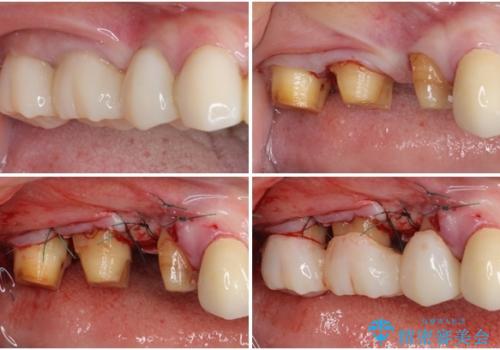

失われていた歯槽骨を、再生治療により可及的に改善させ、その1年後に歯周ポケットを除去するための歯周外科処置を行うこととしました。

処置後はオールセラミックブリッジにて補綴し、再発防止のために就寝時にナイトガード(マウスピース)を装着していただくこととしました。

歯槽骨の再生には1年ほどの待機期間を要し、その後のポケット除去処置も数か月の待機期間を必要とするため、治療期間は長期に及びました。

治療途中からマウスピースを装着していただくことで、歯槽骨の回復も順調に進みました。

術後に痛みの続く処置を2度も受けていただくこととなりましたが、処置後は出血などの気になる症状がなくなり、患者様には大変満足していただきました。